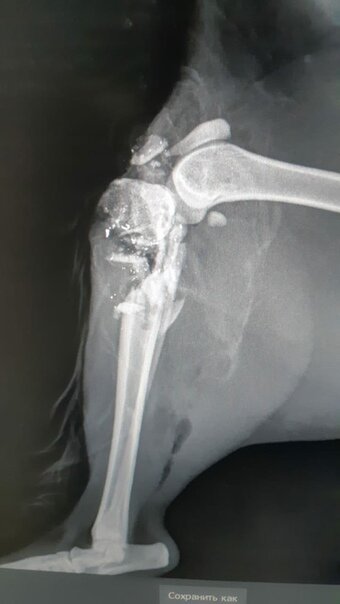

Там было написано, о том что котик сам пришёл к людям с прокушенной задней лапой. Далее котик был доставлен в приют и были сделаны снимки

После осмотра был выявлен: сложный открытый перелом. Кость

Снимок из вет.клиники

После осмотра был выявлен: сложный открытый перелом. Кость была раздробленна на столько, что её было не собрать и не поставить железку. Принято решение, ампутировать заднюю лапу по колено. Позже выяснилось, что это дело человека, которому по какой-то причине помешал кот. Тяжело. Писать тяжело. Думать об этом тоже.